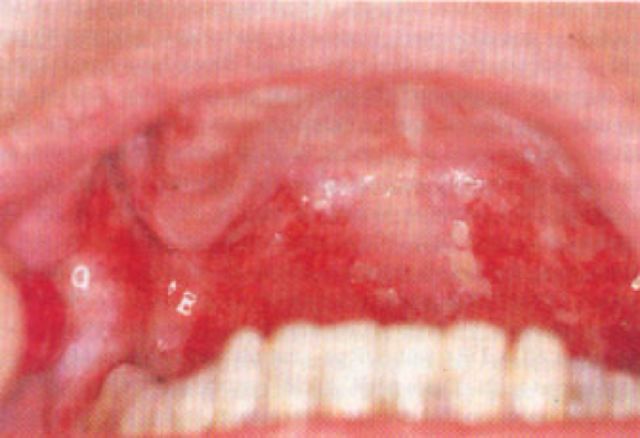

好发在中年人、老年人,少数情况下青年人也可出现。病程大多慢性,早期有可能类似湿疹改变,全身出现散在的红斑、糜烂、水疱。可以伴有或不伴瘙痒。如果按“湿疹”治疗,长期无好转,或者同时出现眼、口腔、外阴等粘膜部位的糜烂、水疱,建议到医院行病理、免疫荧光及特异性抗体检测以确诊。

图2所示是自身免疫性大疱病红斑水疱

图3所示是自身免疫性大疱病口腔黏膜糜烂